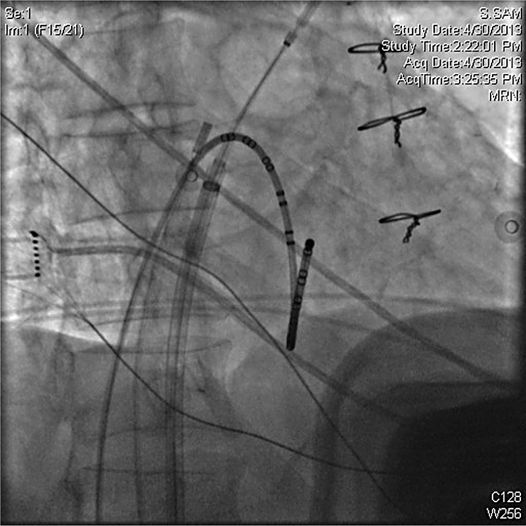

Although this likely reflects the fact that patients with persistent af. Doctors perform cryoablation to restore normal heart rhythm by disabling heart cells that create an irregular heartbeat. Multiple large observational studies and randomized controlled trials have shown that catheter ablation, which is centered on electrical isolation of triggering foci within the pulmonary veins (pvs), is superior to antiarrhythmic drug (aad).

In this procedure, a doctor uses a thin adaptable cylinder, known as an inflatable catheter, to find and fix the problematic portion of the heart. Author information and affiliations last update: To restore normal heart rhythm and treat heart cells that cause atrial fibrillation, cryoablation may be done by your electrophysiologist (ep doctor).

However, all the techniques used during af ablation are not free of complication. Web this randomized study reports that randomization to radiofrequency ablation was associated with less patients experiencing an episode of persistent atrial tachyarrhythmia, as determined by implantable cardiac monitors, compared to. Web cryoablation for atrial fibrillation patients with symptomatic, paroxysmal, untreated atrial fibrillation were randomly assigned to antiarrhythmic drug therapy or cryoablation.